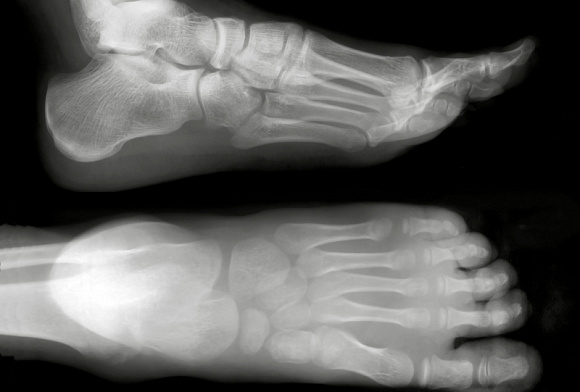

Рентгенография пяточных костей в 1-й проекции (со снимком)

Это рентгенологическое обследования пяточных костей, которое позволяет увидеть строение и структуру, а также исключить травматическую патологию (переломы) и воспалительные изменения, новообразования.